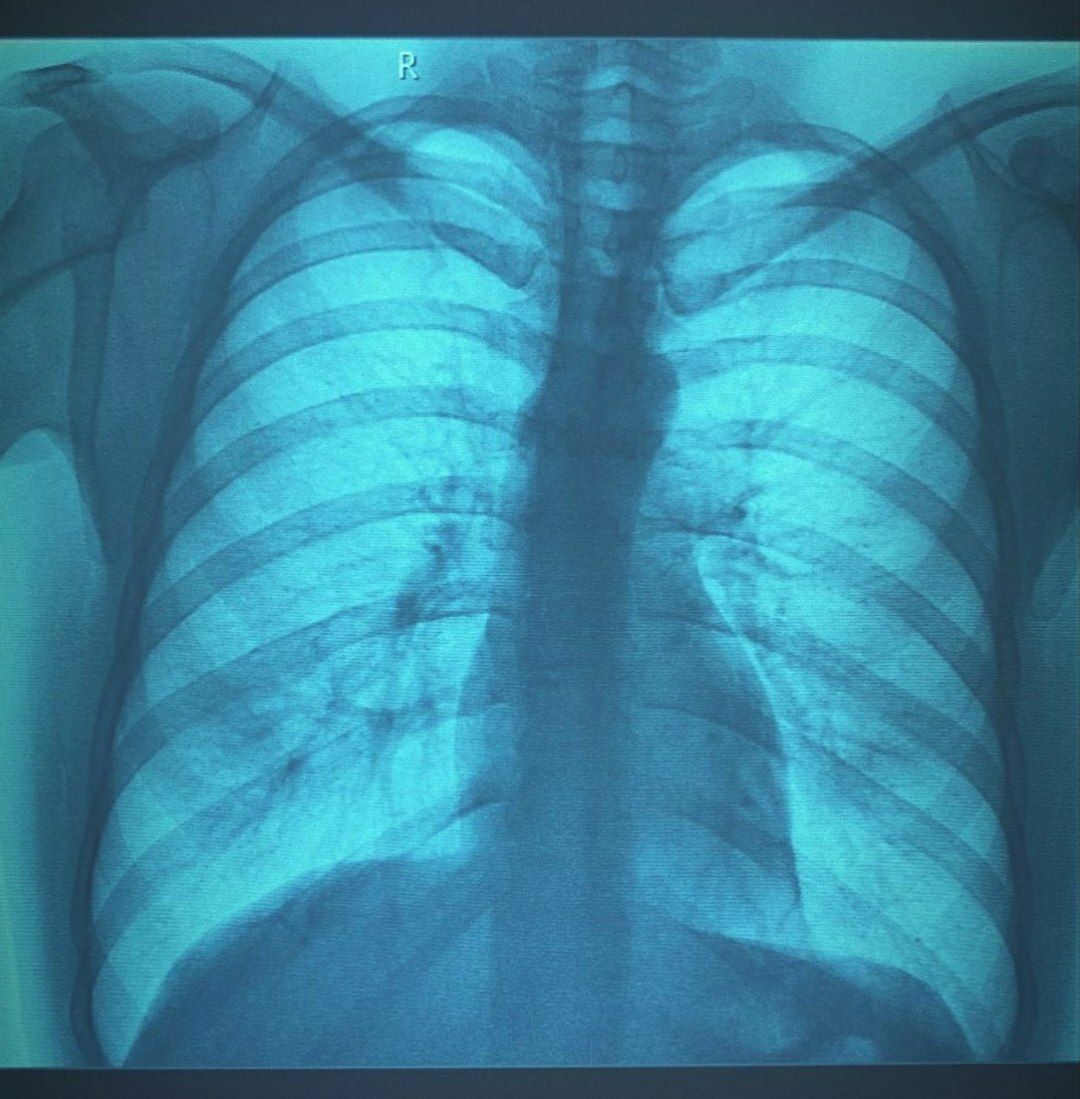

Оцените снимок пожалуйста. На форуме мы спорим с врачом, есть ли тут пневмония или нет. Список ребенка, через неделю после начала заболевания.

Мое мнение, что пневмония здесь не видна (настолько, что бы это можно было смело утверждать). Коллега утверждает, что отлично видна инфильтрация и дольковый ателектаз